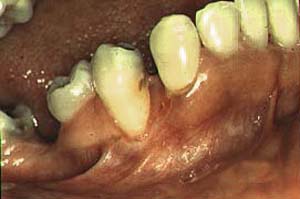

Secuestro óseo |

|